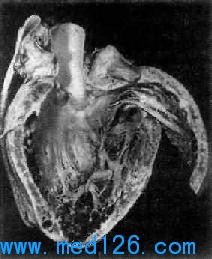

2.病理大量屍檢證實,中國東北、華北、西北及西南各病區的各型克山病的病變特徵基本一致,是以心肌細胞線粒體損害為主的代謝性心肌病變。肉眼觀心臟呈肌原性擴張,心室向兩側普遍擴張,嚴重者呈球形,心室壁常不增厚。切面見心肌實質有互相交織的變性、壞死及纖維化病灶。心內膜有斑片狀增厚,20%的病人有附壁血栓及肺、腦、腎、脾、腸系膜和末梢血管栓塞。心臟瓣膜及冠狀動脈基本正常。光鏡下,可見心肌細胞瀰漫性變性和灶狀壞死,以左心室及室間隔多見,且程度較重,而右心室較輕;心室比心房重;心室內、中層比外層重;急型克山病心內膜下心肌壞死可達95%,但兒童心室中、外層病變比心內膜重。心肌病灶與冠狀動脈的逐級分支密切相關,在兒童亞急型者更明顯。心肌細胞呈顆粒樣變性,其內可有大小不等的空泡變性,或可呈排列整齊的脂肪變性所致的心肌壞死。同一病變中,凝固性及溶解性壞死可混合存在,其中急型重症以凝固性壞死為主,而亞急型則以溶解性壞死為主,常伴有不同程度的繼發性炎症反應。病變可侵犯傳導系統,以雙側束支尤其是右束支病變更嚴重。電鏡主要可見線粒體腫脹、增生,線粒體嵴破壞、心肌細胞外膜系統損害和毛細血管內皮損傷。結合組織化學分析,可見此種病理變化與心肌細胞的氧化、還原代謝系統障礙有關。因此有人認為本病是一種以心肌細胞線粒體損害為主要特徵的原發性代謝性心肌病(心肌線粒體病)。套用心內膜心肌活檢術,對潛在型和慢型克山病心肌行電鏡觀察發現,心肌細胞的膜系統有明顯改變,內質網、T管、閏盤擴張,線粒體增生、異型,肌原纖維異常分支以及微小的肌溶解和間質纖維化等。套用分子生物學技術,在心肌病灶周圍或散在分布有凋亡之心肌細胞,提示心肌細胞凋亡也參與了心肌損害的發生與發展。除心肌外,其他臟器如骨骼肌、肺臟、胰腺、甲狀腺等多為淤血性改變。